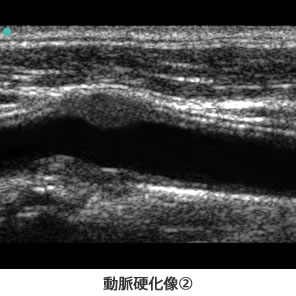

具体的には、動脈壁の(内膜ー中膜複合体)の肥厚、プラーク(1mm以上の壁の肥厚状態)の性状、動脈径の狭窄率を測定し動脈硬化を評価します。また、同時に頚動脈の血流速度を測定し、頭蓋内の血管の状態を推定する事ができます。